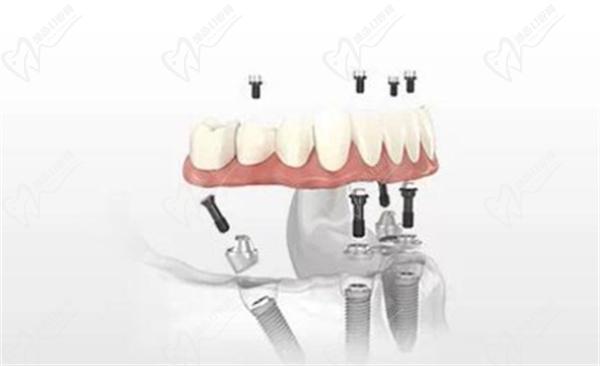

All-on-4是一种即刻种植牙技术,它指的是在全口牙齿缺失的情况下,通过在上下颌骨的4个位置植入种植体,以支持全口义齿或部分义齿的修复。

All-on-4主要适用于全口牙齿缺失的情况,还可以适用于牙槽骨密度较低或缺乏牙槽骨高度或宽度的患者。通过斜向的种植体布局,All-on-4技术可以充分利用可用的牙槽骨,并且不需要进行复杂的牙槽骨移植手术。这减少了手术的痛苦和恢复时间,使更多的患者能够享受到种植牙的益处。

All-on-4的优点在于其即刻修复的成效佳,可以快速恢复患者的咀嚼功能和面部形态。同时,由于其使用的材料强度较高,可以承受较大的咬合力。但是,由于其手术风险较大,植入过程较复杂,患者术后反应较明显。

相比传统的马龙桥手术,All-on-4的优势在于可以减少手术时间和费用,降低手术的复杂性和创伤。通过合理的种植体位置和角度安排,All-on-4技术还能够至大限度地利用现有的牙槽骨,并促进牙槽骨的再生。

总结起来,马龙桥和All-on-4都是不错的牙齿修复技术,它们都可以恢复缺失的牙齿,提供良好的咀嚼功能和美观度。马龙桥采用6到8颗种植体,手术复杂耗时长,适用于不同种植情况的患者;而All-on-4只使用4颗种植体,手术简化,适用于牙槽骨密度较低的患者。选择合适的治疗方案应该根据患者的具体情况来综合考虑,与正规口腔医生进行详细咨询和讨论。